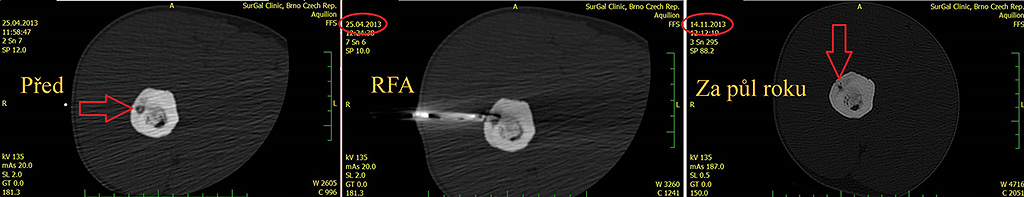

Obr. 3 Radiofrekvenční ablace osteoidního osteomu na CT zákrokovém sále

Obr. 4 Kontrola po roce, patrná je sklerotizace nidu osteoidního osteomu